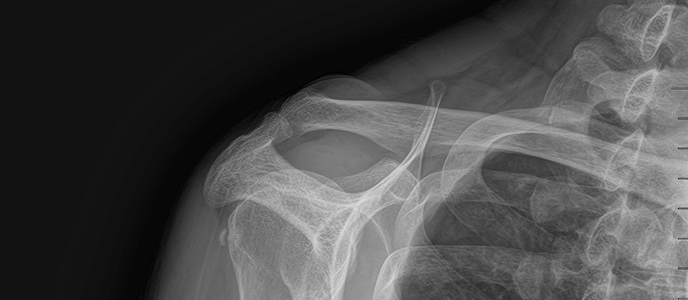

치료 증상 자고 나서 팔을 들기 힘들 정도의 심한 어깨 통증

나이/성별 45세 / 남성

치료 내용 석회쇄석흡인술 후 호전

치료 기간 2024-09-12 ~ 2024-12-18